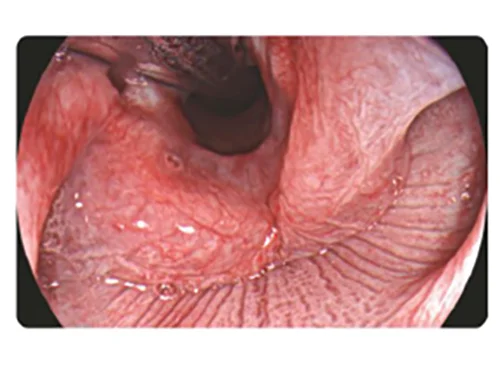

TEI: Визуализация с улучшением текстуры и цвета

В спектре белого света применяются такие алгоритмы, как корректировка текстур, выравнивание яркости и цветовое выделение, для повышения контрастности изображения, выделения тона и структуры поражения, повышения эффективности отображения и улучшения цвета, текстуры и структуры слизистой оболочки

Применение

- Диагностика воспалений и плоских блюдцеобразных поражений

- Изучение морфологии слизистой оболочки для обнаружения поражений.

Белый свет

TEI